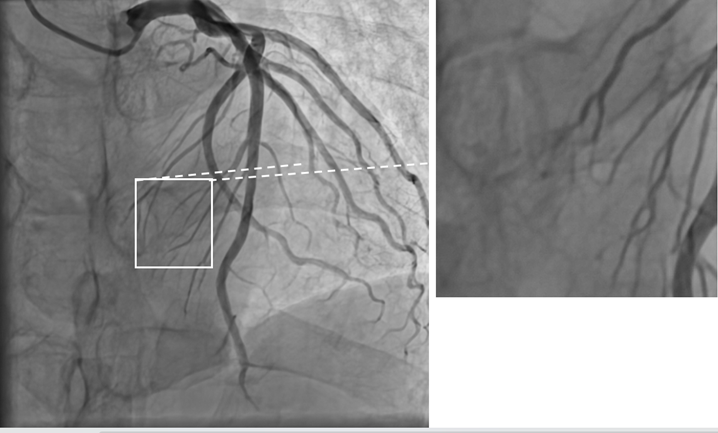

此次全新升级的“零噪声”DSA设备,凭借软硬件同时的系统优化升级,搭载国产自研高压发生器与智能滤过系统,利用多帧融合降噪原理,实现了图像质量的飞跃式提升,它几乎完全消除了图像中的干扰性噪点,图像空间分辨率提升57%,信噪比提升超过4倍。这意味着医生能够像拥有“超级显微镜”一样,更清晰地观察到血管内的微小结构和病变情况。以冠脉造影为例,以往难以察觉的间隔支、对角支等侧支小血管,以及0级和1级侧支循环,如今都能清晰显像。在心血管介入手术中,医生可以更精准地定位病变部位,制定出更科学合理的治疗方案,大大提高了手术成功率。

冠脉影像,脉络分明

在冠脉造影手术中,“零噪声”DSA通过硬件技术与深度学习算法协同创新,将空间分辨率从传统DSA的0.2mm级提升至0.1mm级,实现了对冠状动脉微小分支的超高清显影。

“零噪声”DSA“还原真实血管影像”